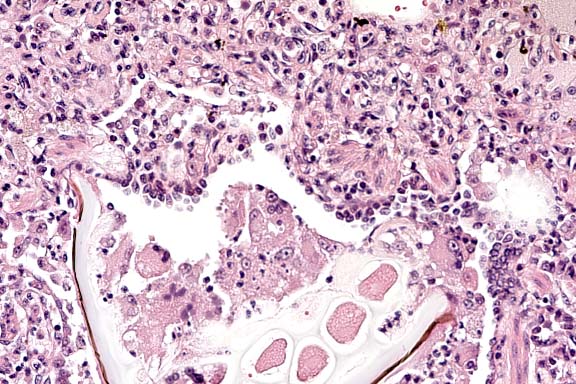

Case 27-4a. Lung. A bacterial colony and many neutrophils are plugging a small artery. and the neutrophils are transmigrating the vessel wall (bacterial embolus with necrotizing vasculitis) into the adventitia and interstitium. 40X

Case 27-4b. Lung. Foreign (plant) material plugging a bronchiole is accompanied by multinucleated giant cells. 20X

1. Lung: Pneumonia, necrosuppurative, embolic, multifocal, moderate, with necrotizing vasculitis, fibrin thrombi, and numerous cocci, rhesus monkey (Macaca mulatta), primate.

2. Lung: Bronchopneumonia, granulomatous, multifocal, moderate, with foreign material.

Conference Note: Conference participants discussed the importance of recognizing that two distinct processes are evident. One process is chronic, bronchocentric, and a result of foreign material introduced into the airways. The other process is more acute, angiocentric, and a result of staphylococcal bacteremia.